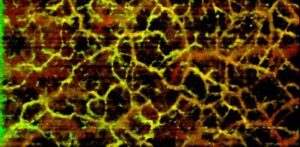

OCT angiography scans captured with the Cobra-S 800 exhibit reduced motion artifacts due to the high speed of imaging, in addition to high resolution.